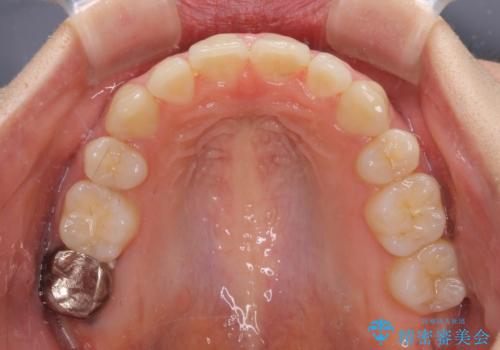

抜歯矯正を行ったことで、デコボコが改善されただけでなく、口元も下がったことで口が閉じやすくなりました。